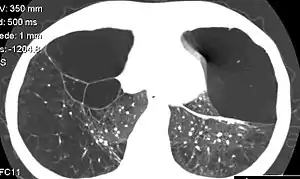

Individuals with A1AD may develop chronic obstructive pulmonary disease (emphysema) during their thirties or forties even without a history of smoking, though smoking greatly increases the risk.[7] Symptoms may include shortness of breath (on exertion and later at rest), wheezing, and sputum production. Symptoms may resemble recurrent respiratory infections or asthma.[8]

A1AT is mainly produced in the liver, with some produced by enterocytes and monocytes,[9] and one of its functions is to protect the lungs from neutrophil elastase, an enzyme that can disrupt connective tissue.[7] Normal blood levels of alpha-1 antitrypsin may vary with analytical method but are typically around 1.0-2.7 g/l.[12] In individuals with PiSS, PiMZ and PiSZ genotypes, blood levels of A1AT are reduced to between 40 and 60% of normal levels; this is usually sufficient to protect the lungs from the effects of elastase in people who do not smoke. However, in individuals with the PiZZ genotype, A1AT levels are less than 15% of normal, and they are likely to develop panlobular emphysema at a young age. Cigarette smoke is especially harmful to individuals with A1AD.[7] In addition to increasing the inflammatory reaction in the airways, cigarette smoke directly inactivates alpha-1 antitrypsin by oxidizing essential methionine residues to sulfoxide forms, decreasing the enzyme activity by a factor of 2,000.

A1AT deficiency remains undiagnosed in many patients. Patients are usually labeled as having COPD without an underlying cause. It is estimated that about 1% of all COPD patients actually have an A1AT deficiency. Testing is recommended in those with COPD, unexplained liver disease, unexplained bronchiectasis, granulomatosis with polyangiitis or necrotizing panniculitis.[10] American guidelines recommend that all people with COPD are tested,[10] whereas British guidelines recommend this only in people who develop COPD at a young age with a limited smoking history or with a family history.[14] The initial test performed is serum A1AT level. A low level of A1AT confirms the diagnosis and further assessment with A1AT protein phenotyping and A1AT genotyping should be carried out subsequently.[11]